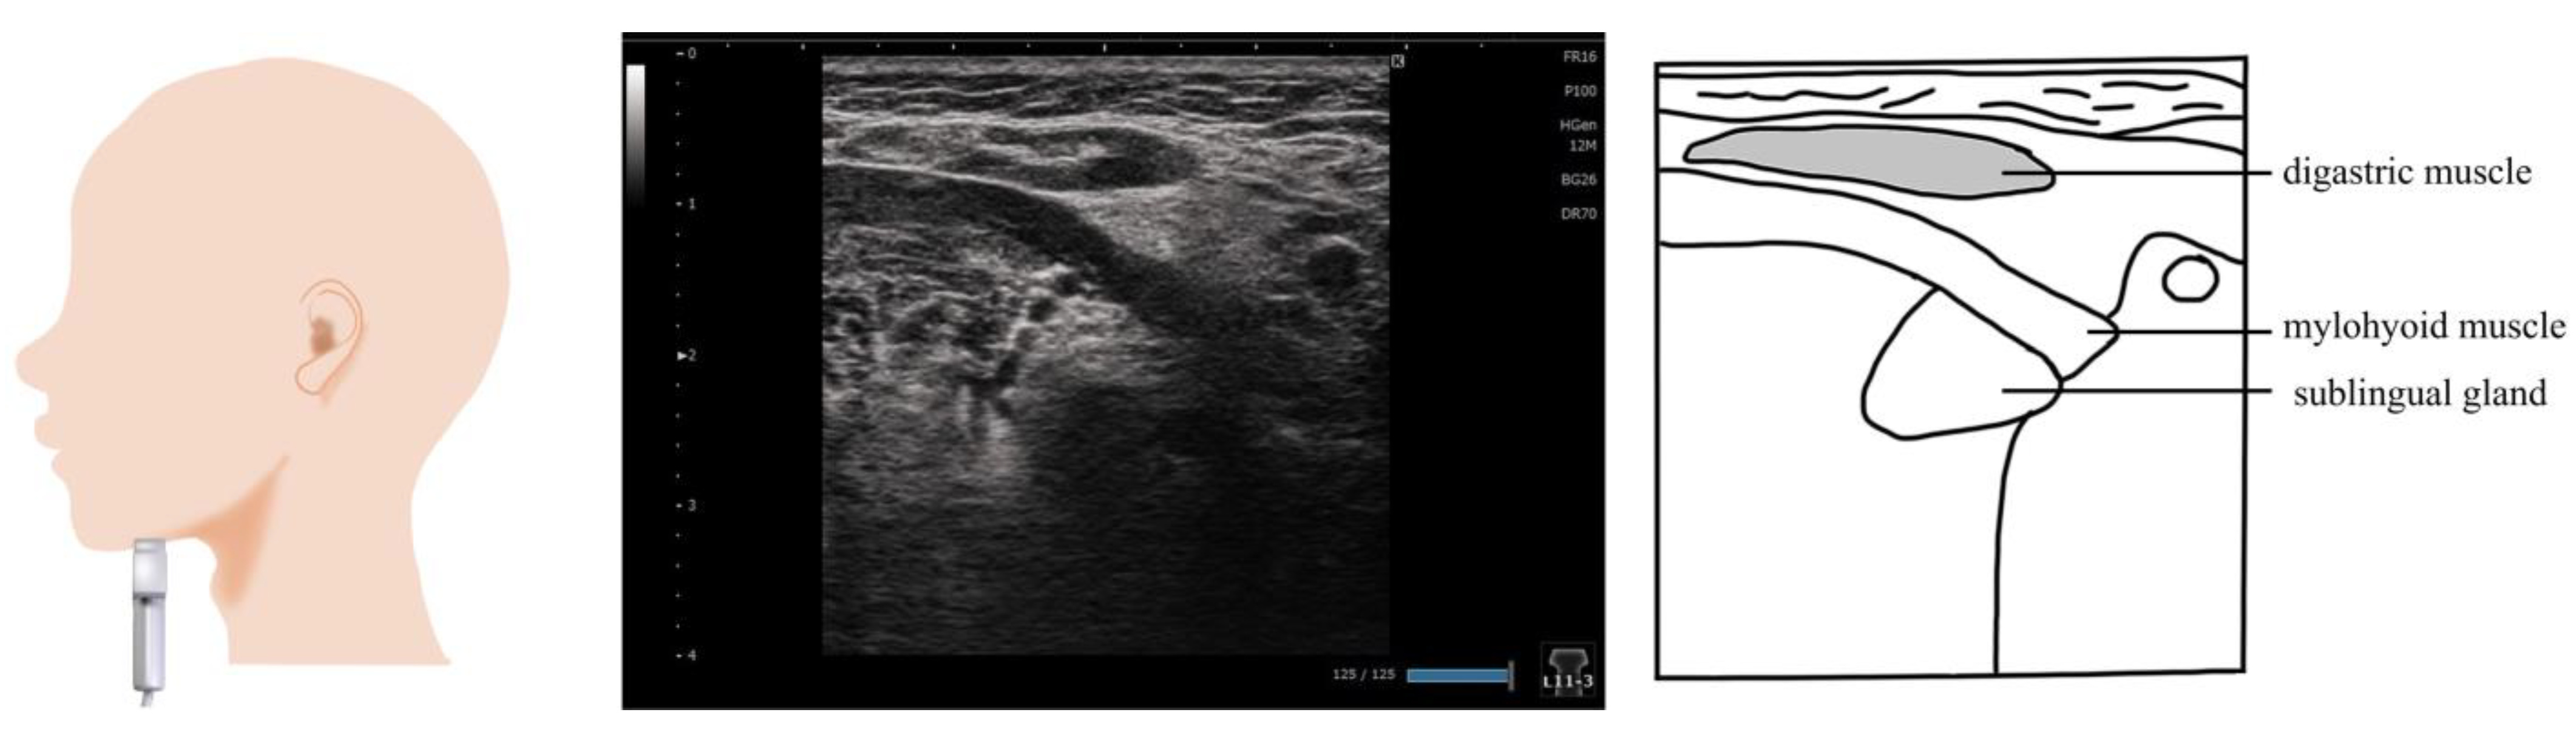

3. Digastric Muscle (Figure 2)

4. Mylohyoid Muscle (Figure 3)